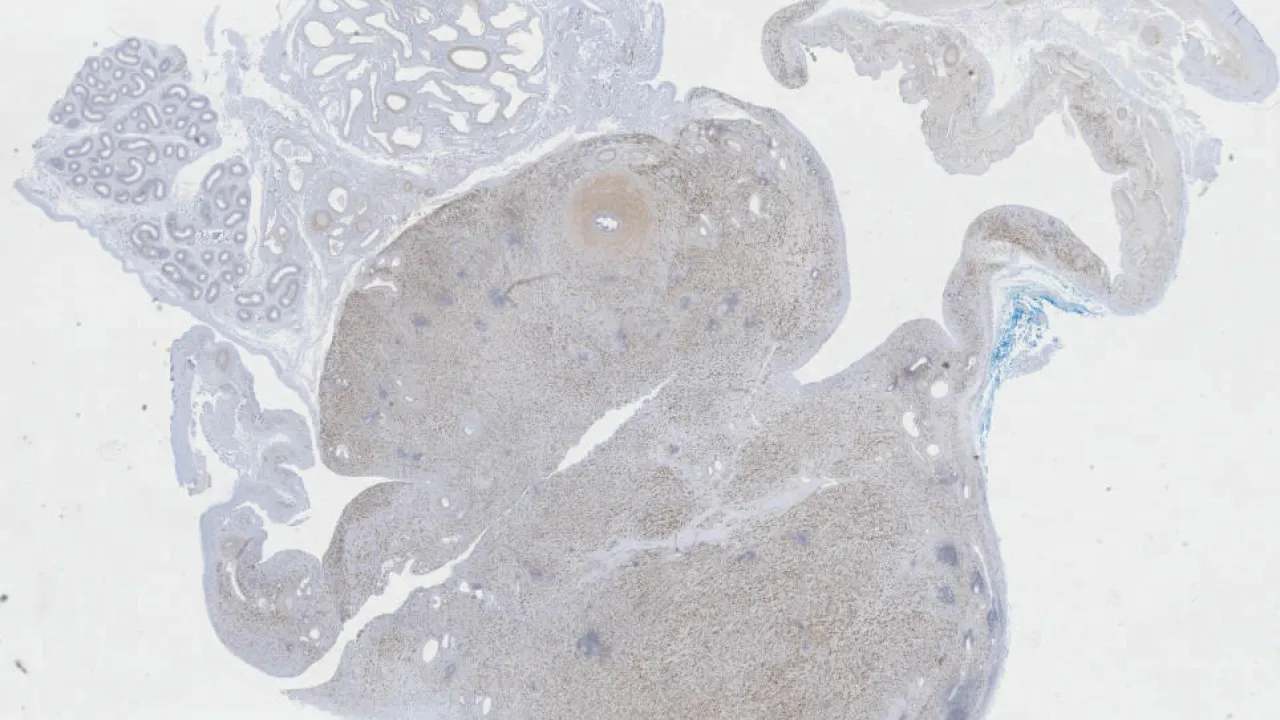

Brain, IgG4-related hypophysitis